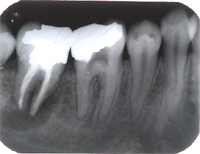

Im Röntgenbild von Abb. 3 ist ein gut erbsengrosses Granulom (Pfeil) an der Wurzelspitze eines toten, devitalen Zahnes feststellbar. Die Patientin wünschte die Erhaltung des Zahnes, zumal auch der vordere Nachbarzahn marktot und beherdet war. Abb. 4 zeigt das Röntgenbild nach der Wurzelfüllung.